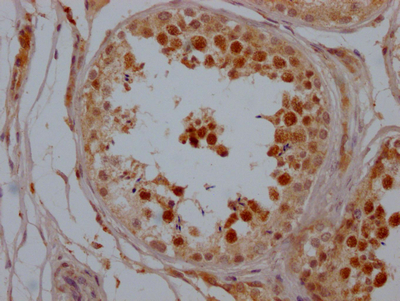

IHC image of CSB-RA556800A0HU diluted at 1:100 and staining in paraffin-embedded human testis tissue performed on a Leica BondTM system. After dewaxing and hydration, antigen retrieval was mediated by high pressure in a citrate buffer (pH 6.0). Section was blocked with 10% normal goat serum 30min at RT. Then primary antibody (1% BSA) was incubated at 4℃ overnight. The primary is detected by a Goat anti-rabbit IgG polymer labeled by HRP and visualized using 0.05% DAB.